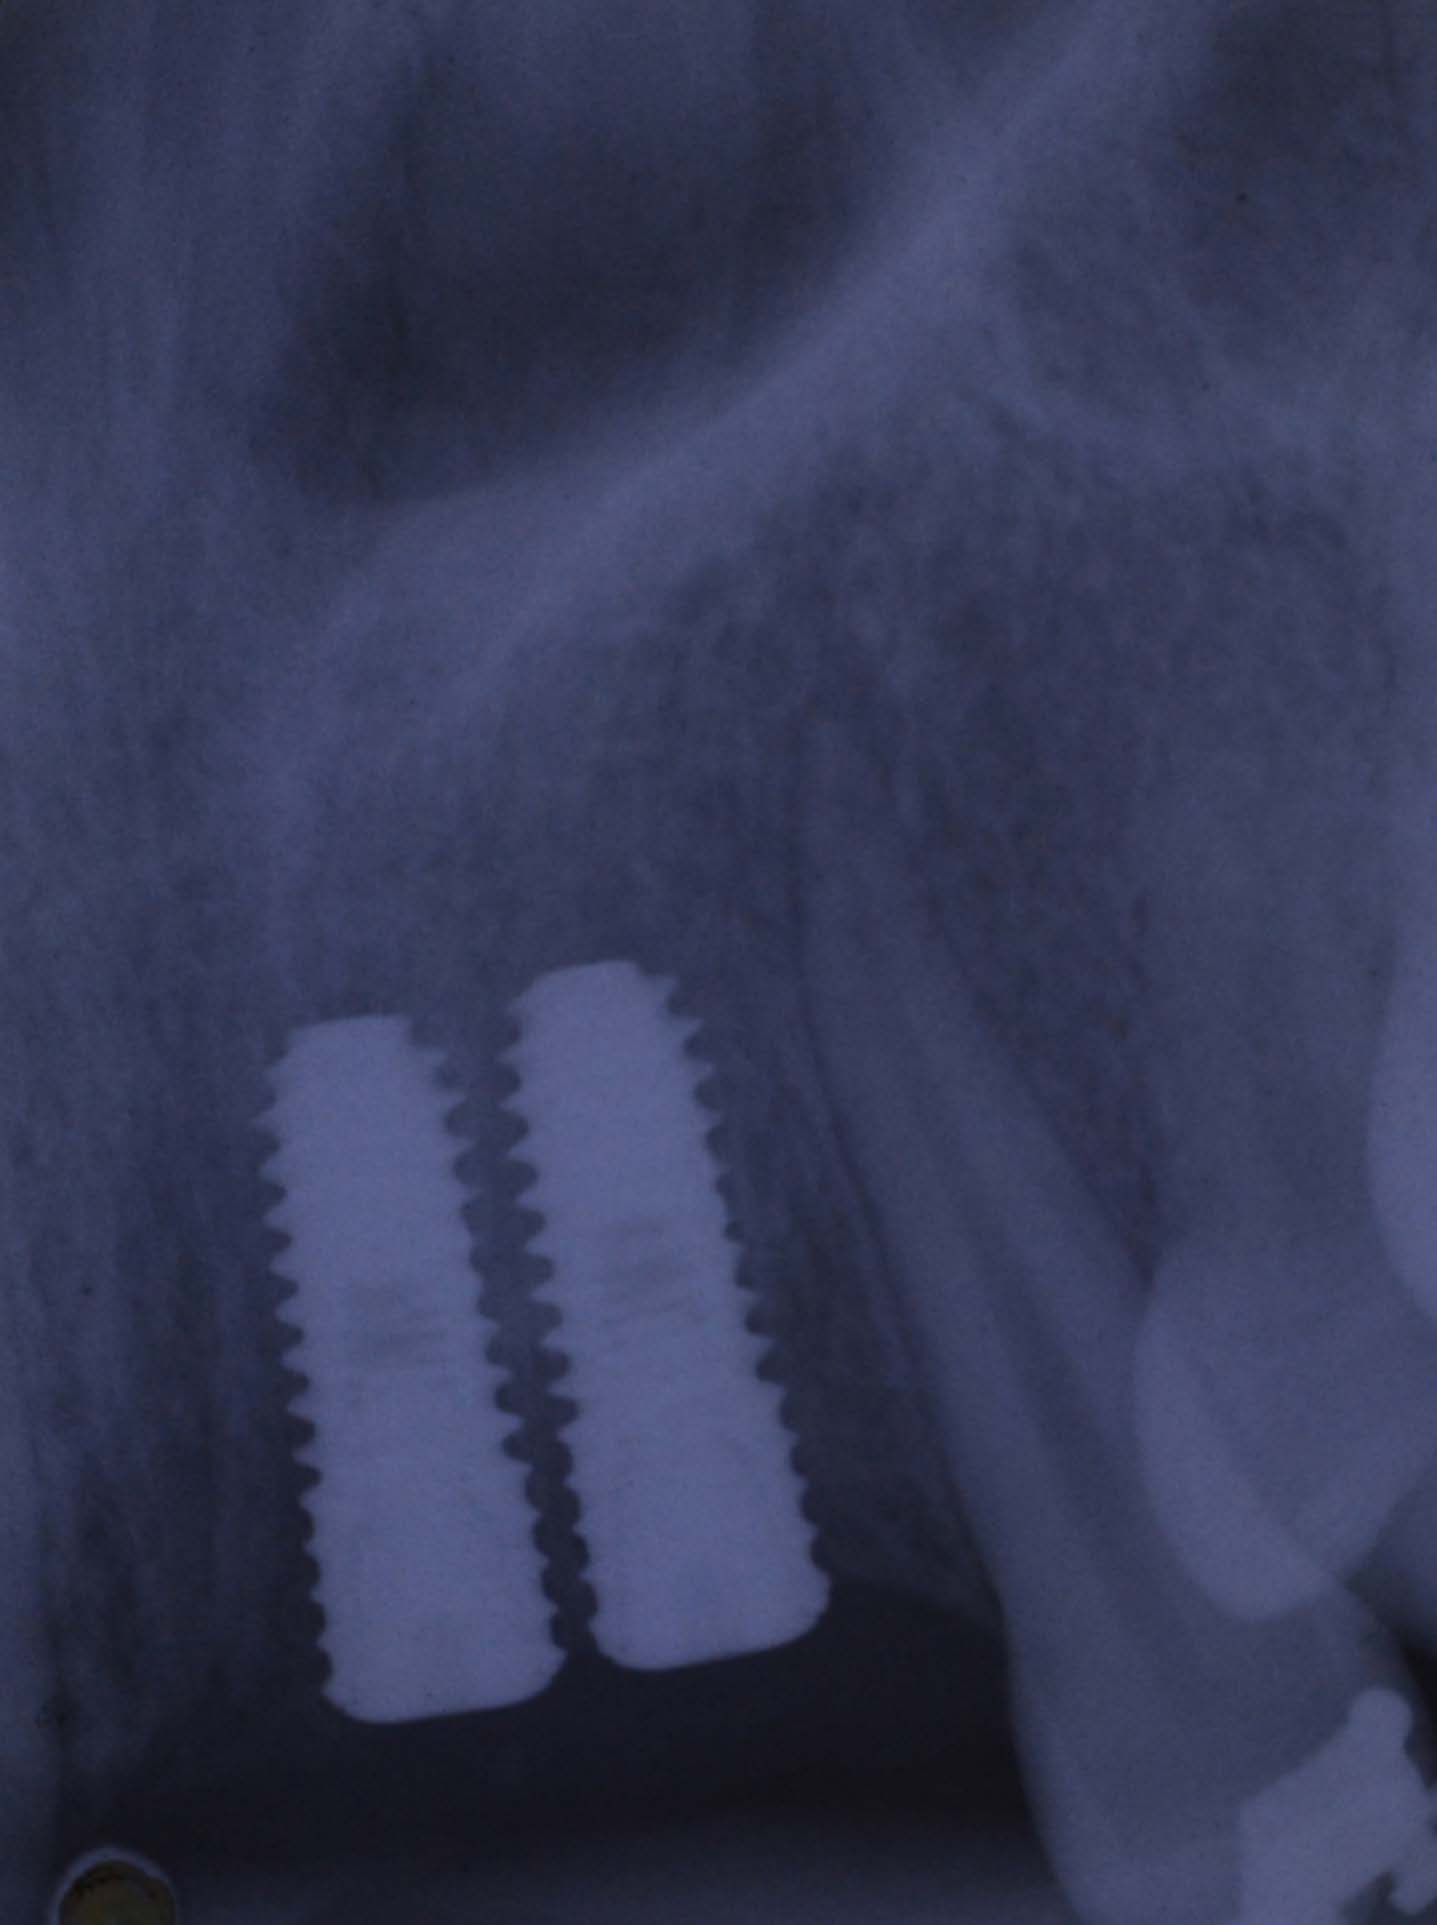

The complete encirclement around implant ensured non mobility of the PRF membrane and persistent positioning in close proximity to the crestal bone ensuring maximal beneficial effect in the crestal bone area during healing period [Table/Fig-4,5].

Intra oral peri apical radiograph depicting the crestal bone in early placed dental implant in post extraction site.

Intra oral peri apical radiograph depicting the crestal bone after three months of immediately placed dental implant augmented with Platelet Rich Fibrin (PRF) membrane at juxta-crestal bone around dental implant.